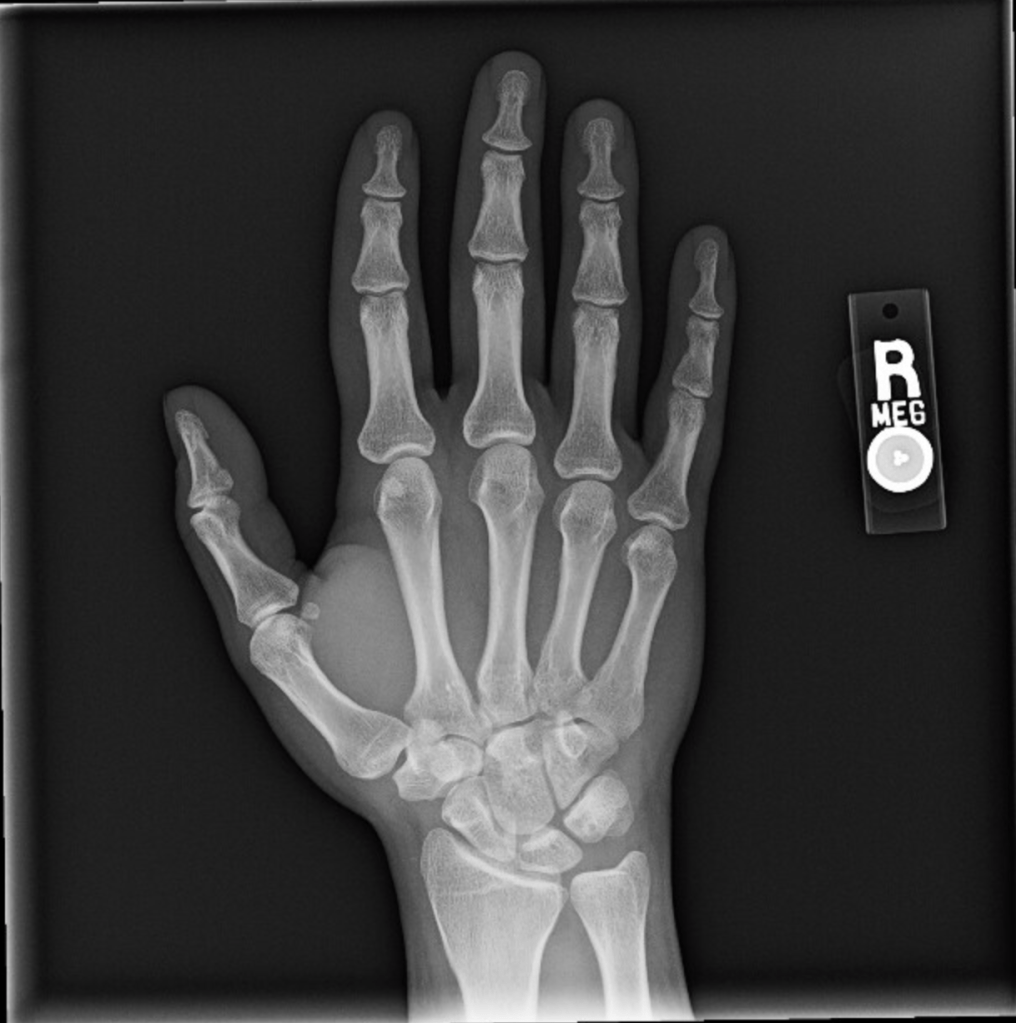

The reason I injured my wristโresulting first in probable tendonitis that made it basically impossible to use my right hand and then some mysterious secondary condition(s) that initially meant my left arm got really sore really easily and now is more of a joint thing that’s affecting both my hands and, to a lesser extent, all of my joints, but is probably not arthritis based on preliminary blood tests (my doctor thinks it’s carpal tunnel, but the test for that is booked until June)โis definitely not at all embarrassing, not at all something that I had advance warning of and could have easily avoided if I’d just listened to what my body was telling me, definitely don’t click that arrow.

I wake up in the morning with an odd discomfort in my right pinkyโwhen I unbend it, I get this weird kind of clicking feeling at the base. It's a little distressing but goes away after about an hour, so I ignore it. And sure my wrist hurts from all the tiny handwriting...and the several hours of Elden Ring and/or Need For Speed Unbound I play in between writing sessions, but I keep stretching it out and figure that's good enough. And I keep on that way through Friday as wellโafter waking up with the same weird pinky issue. Which I also have Saturday morning.

At this point I'm pretty sure something's going on, so I scale things back, but it's not until I wake up on Sunday feeling downright sore that I put a stop to all nonessential wrist functions. I call out of work, take the day to rest, go to bed early, and figure I'll feel basically fine tomorrow.

At approximately 11:30 pm I wake up and can't move the fingers on my right hand.

So April 3rd is my first appointment with the hand specialist. My assumption for how this is going to go is that I’m going to explain my symptoms and he’s going to say, “Yeah, that’s pretty standard for this kind of injury, here’s some sort of medication or some other specific treatment and a referral for physical therapy.” That is not what happened. After I explained my symptoms he had me do all these movements with my hands that the urgent care physician had had me do and had then told me that I definitely didn’t have carpal tunnel, and so of course the hand specialist tells me he thinks it’s carpal tunnel. “So the test for that is a nerve conduction study, those usually take a while to open up so we’ll try to get that process started as soon as possible, and in the meantime we can run some more blood tests just to rule out arthritis.” “How long is a while?” “Probably two months.”

- It has, at time of writing, been 13 weeks. My nerve study is in 4 days. My next doctor’s appointment to discuss the results is in a week. My hands are still hurting.